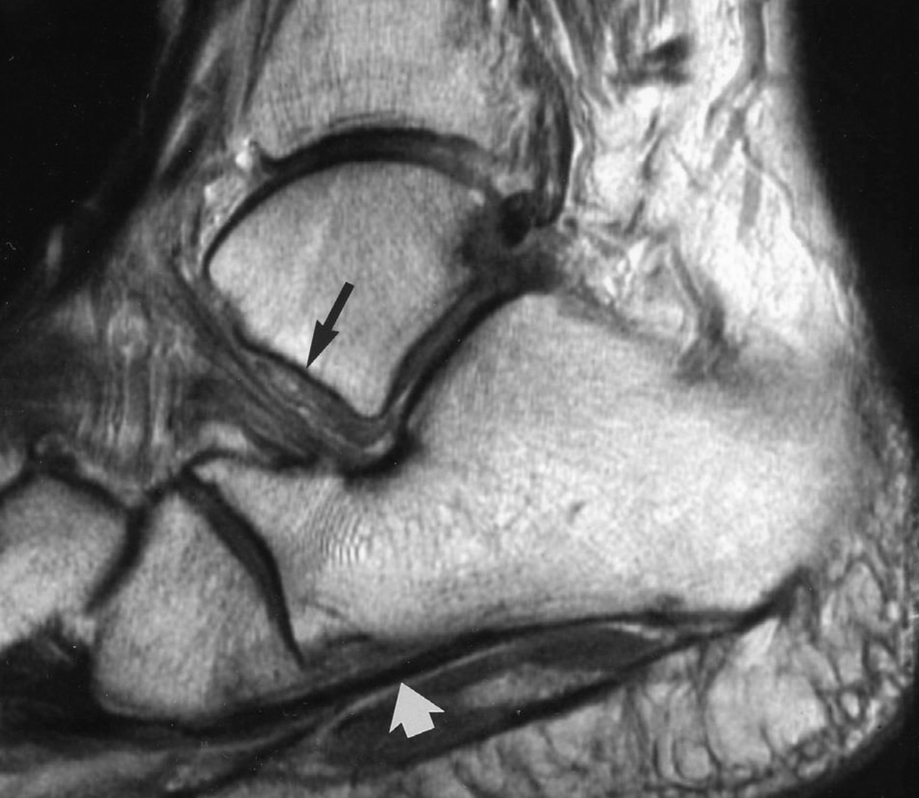

The Adult Acquired Flatfoot Springerlink